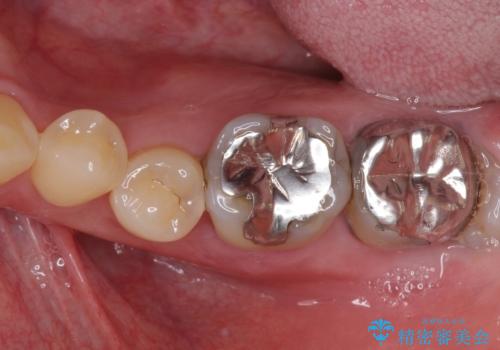

- 上下前歯の反対咬合と左下奥歯の痛みを気にして来院された患者様です。

また、左下の奥歯は親知らずの影響で手前の歯の歯根までむし歯になってしまったため、親知らずとともに抜歯をし、インプラントによる補綴治療を行うこととしました。

インプラント埋入による仮歯の装着や、前歯の反対咬合の改善は比較的スムーズに達成されましたが、舌突出癖などの影響による、歯列全体のスペースを閉じることが難航し、期間がかかってしまいました。